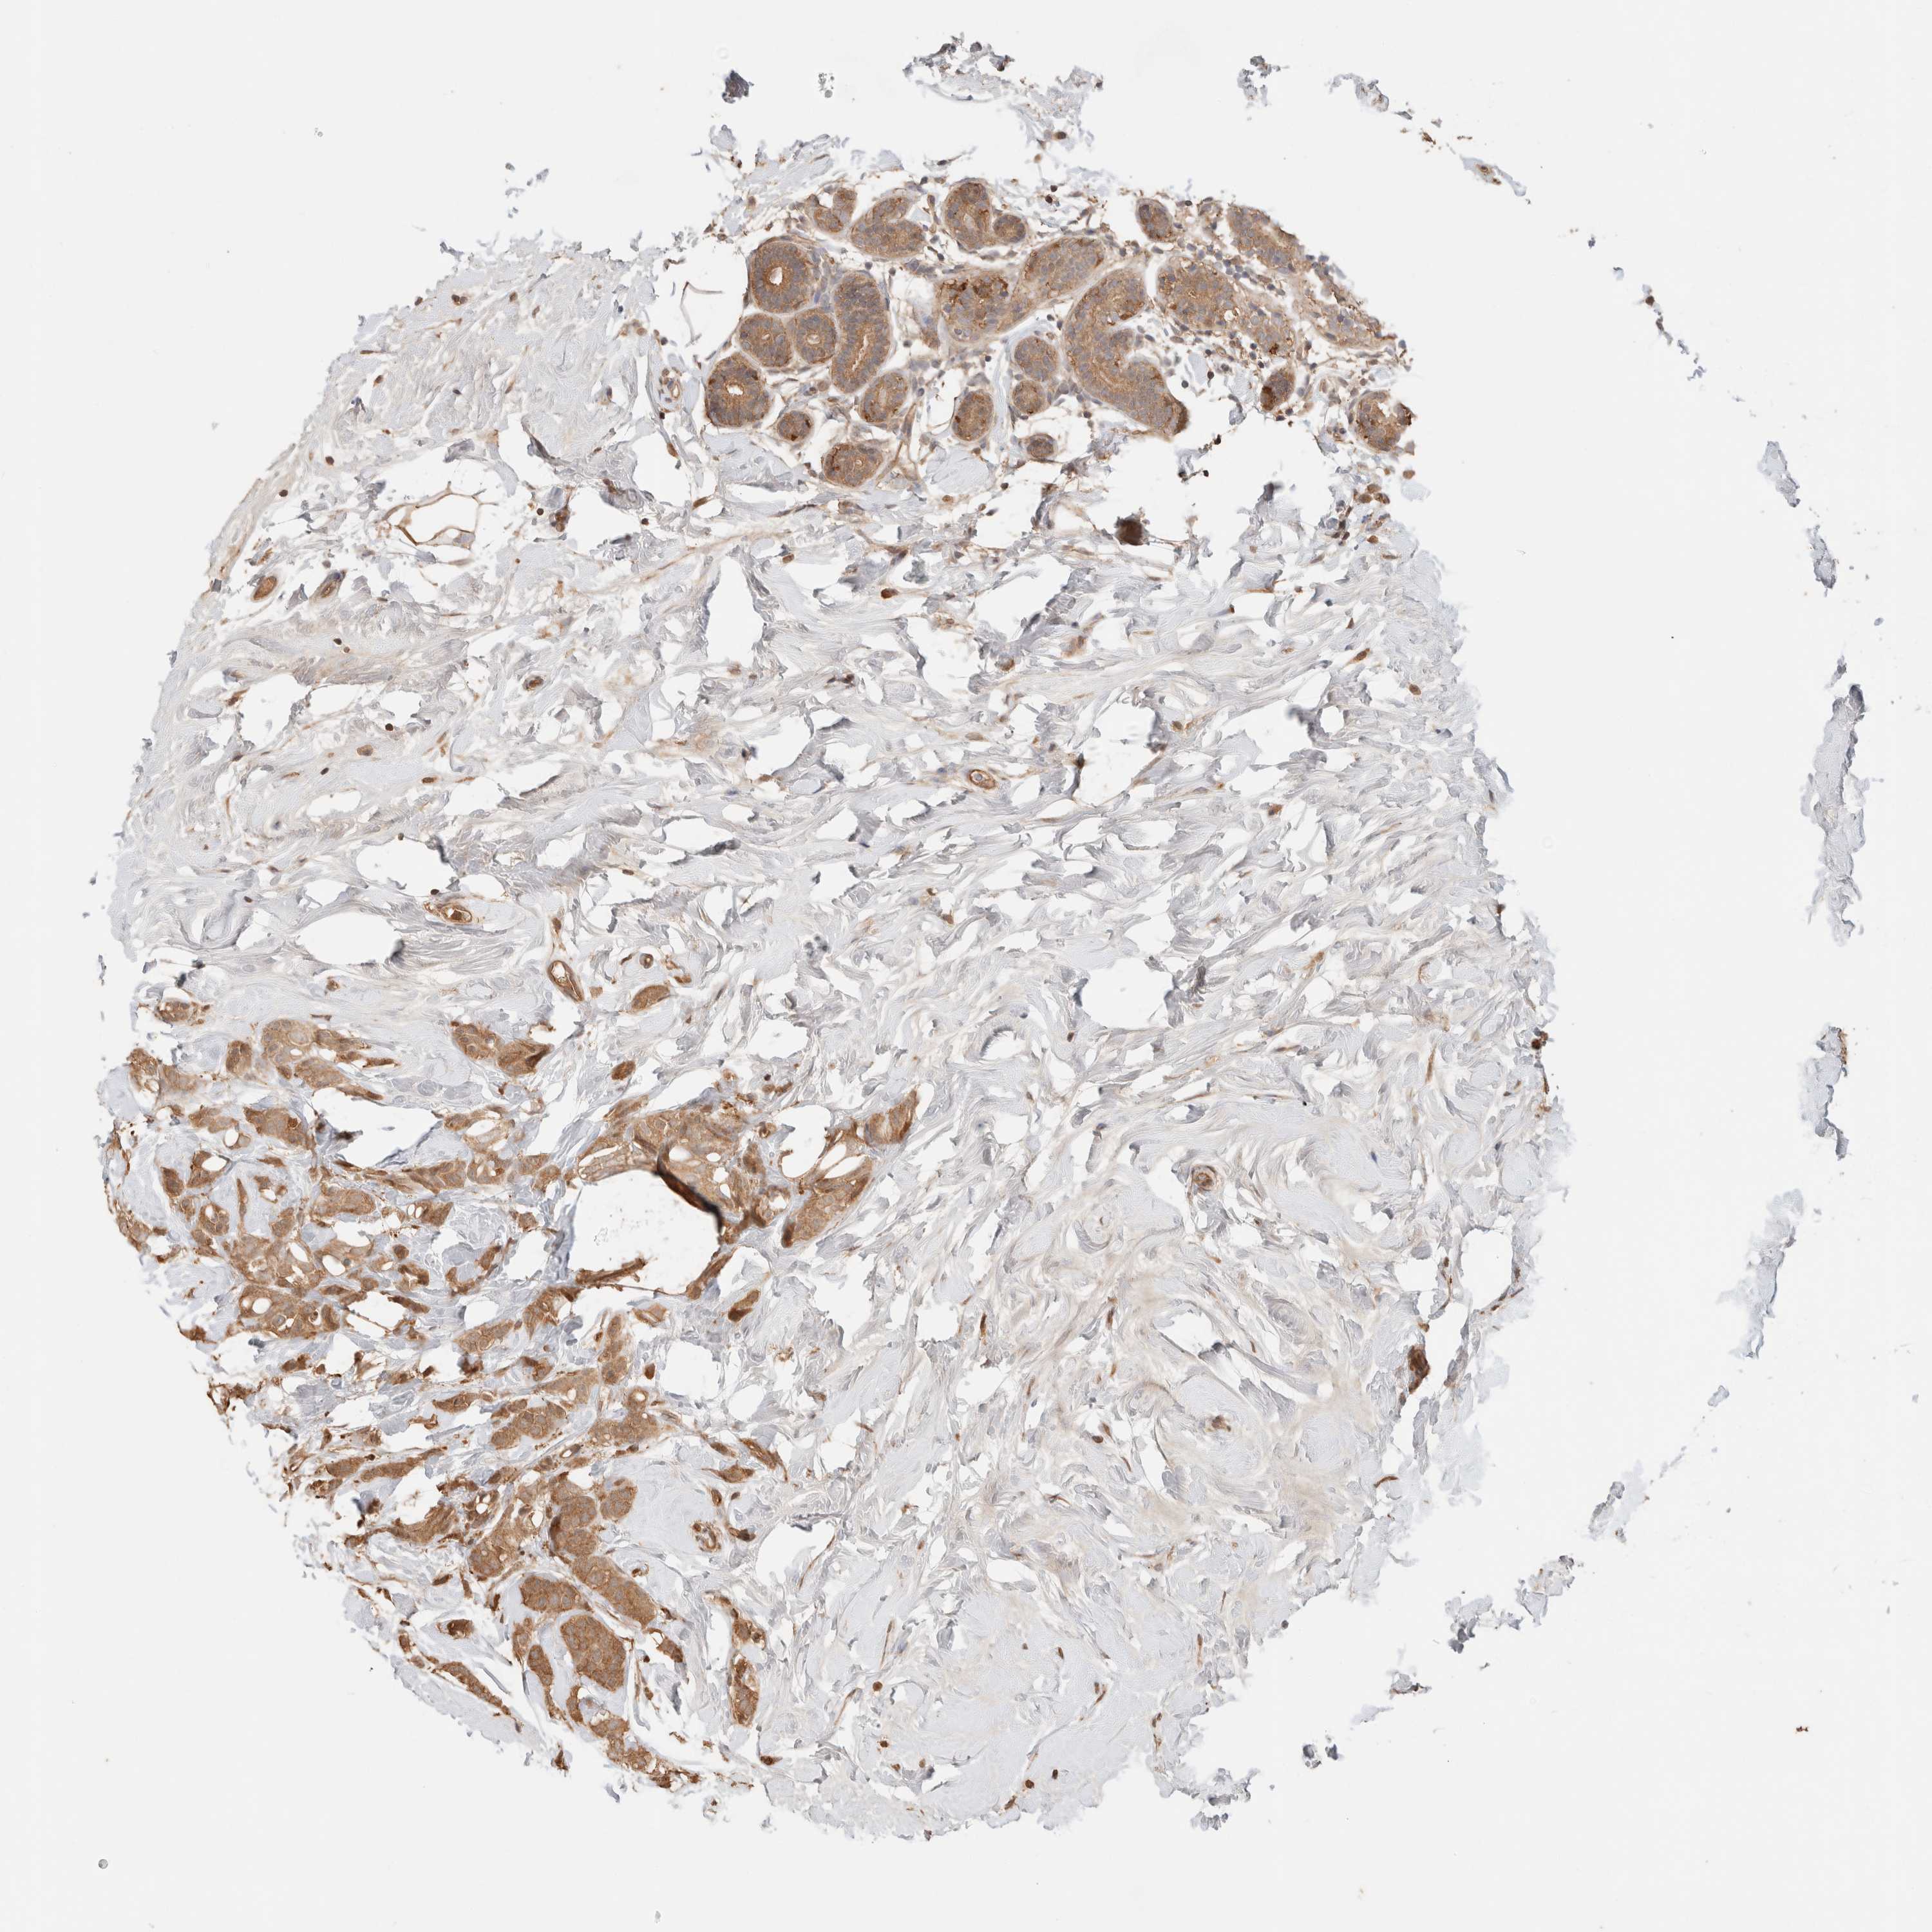

CANCER BREAST CANCER Show tissue menu

BRCA TCGA BRCA VALIDATION PROTEIN EXPRESSION